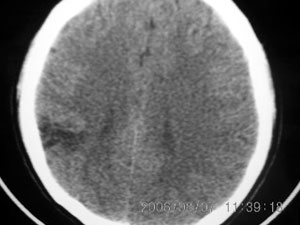

标题: CT4285:头部病变,女 21岁 [打印本页]

标题: CT4285:头部病变,女 21岁

女 21岁 发作性面色发白一年,每次发作仅数秒钟

脑血管畸形,建议做增强

脑软化灶可能性大.

局限性脑软化灶、脑萎缩,考虑动静脉畸形。

建议mri增强检查,不排除dnt可能。

局部软化灶,脑沟增宽加深,考虑为脑血管畸形可能,建议增强或mri检查.

左颞顶叶不规则低迷度影边界尚清楚,岁数年轻,应考虑脑血管畸形。建议强化或核磁,进一步检查。

考虑脑血管畸形可能,建议mr

局限性脑软化灶,右侧侧脑室后角受吸引,略有拉伸。考虑动静脉畸形。

首先考虑avm,但脑囊虫病有没有可能?